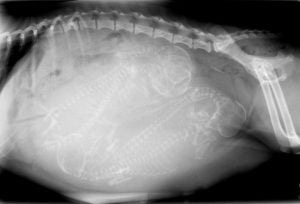

radiologyAt Pleasant Ridge Pet Hospital in Cincinnati, we are proud to be on the cutting edge of medical technology. Digital radiology is a technique and diagnostic tool that we use to look inside the body in a completely non-invasive way and the use of digital dental radiology is a powerful tool for veterinarians who provide pets with dental care. In other words, the use of digital radiology gives us a view of the internal workings of your pet’s body that we otherwise could not see with the naked eye. It’s an important diagnostic tool that helps veterinarians detect disease.

Dental radiology allows us to detect disease below the gumline so that we can diagnose and treat dental disease more accurately. The use of digital radiology is safe and our entire staff is highly trained. It is our goal to provide your pet with the highest level of medical care possible, and this is just one of the many ways we achieve that.